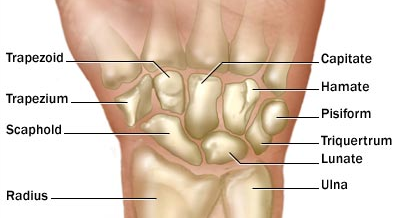

A 19 year old male presents with a humeral fracture after falling off his bicycle. Physical examination reveals inability to abduct his arm to 90 degrees. What nerve was likely affected by this fracture and what muscles are affected?

The axillary nerve, causing a motor deficit in the deltoid.

A 39 year old female presents after a car accident with a mid-shaft humeral fracture. Why might someone just waking up after a long night of drinking have similar symptoms as she does? Why do they have these symptoms?

Both can cause radial nerve palsy. This affects the “BEST extensors” - Brachioradialis, Extensors of wrist and fingers, supinator and triceps. Dennervation of these muscles results in wrist drop and loss in sensation over the dorsum of the hand and posterior arm.